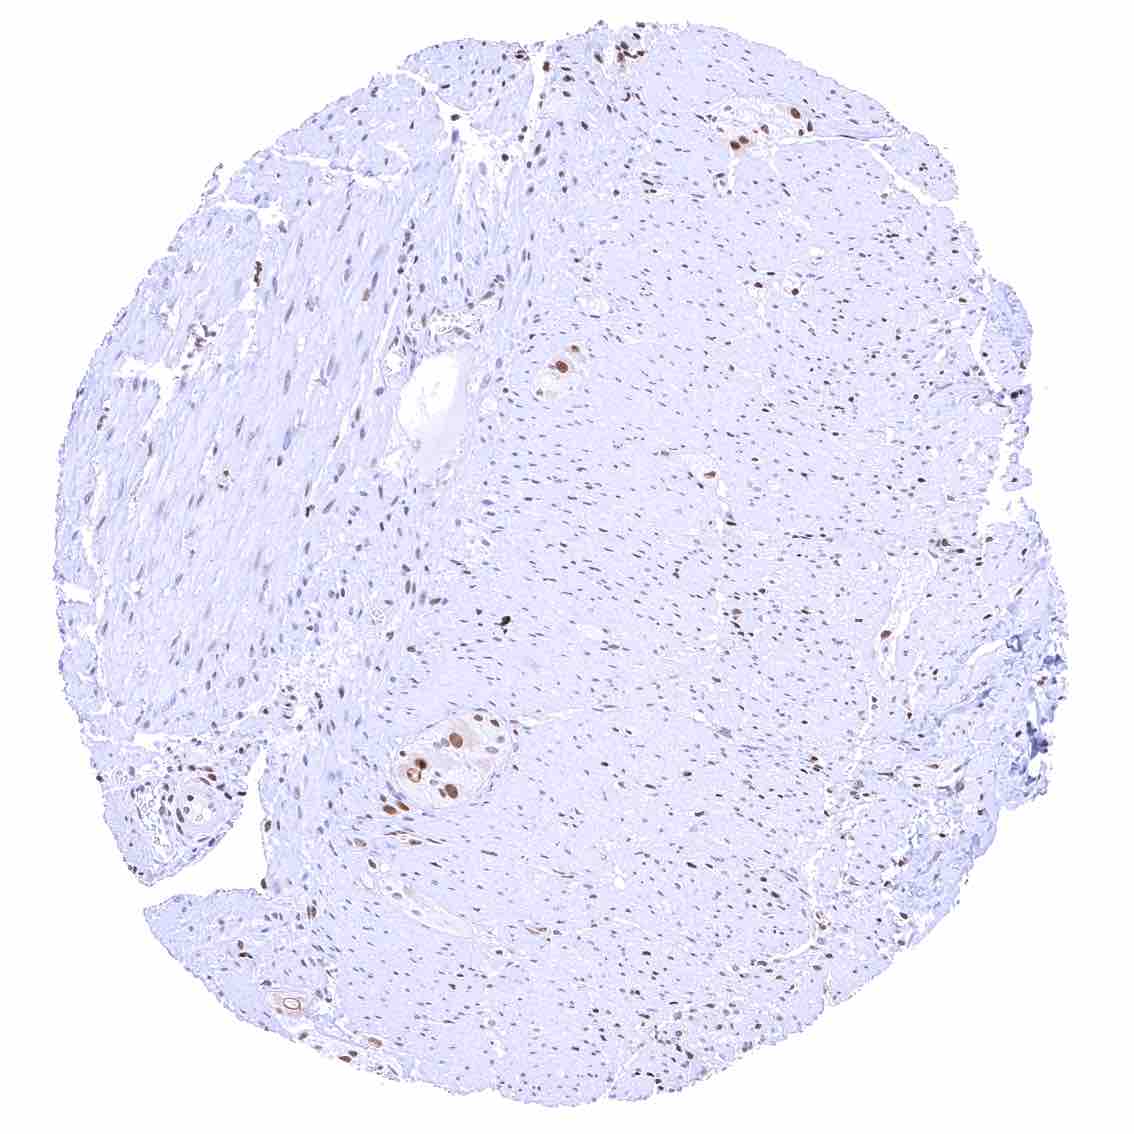

Heart muscle – Distinct nuclear p27 staining of stroma cells while myocytes are largely negative.